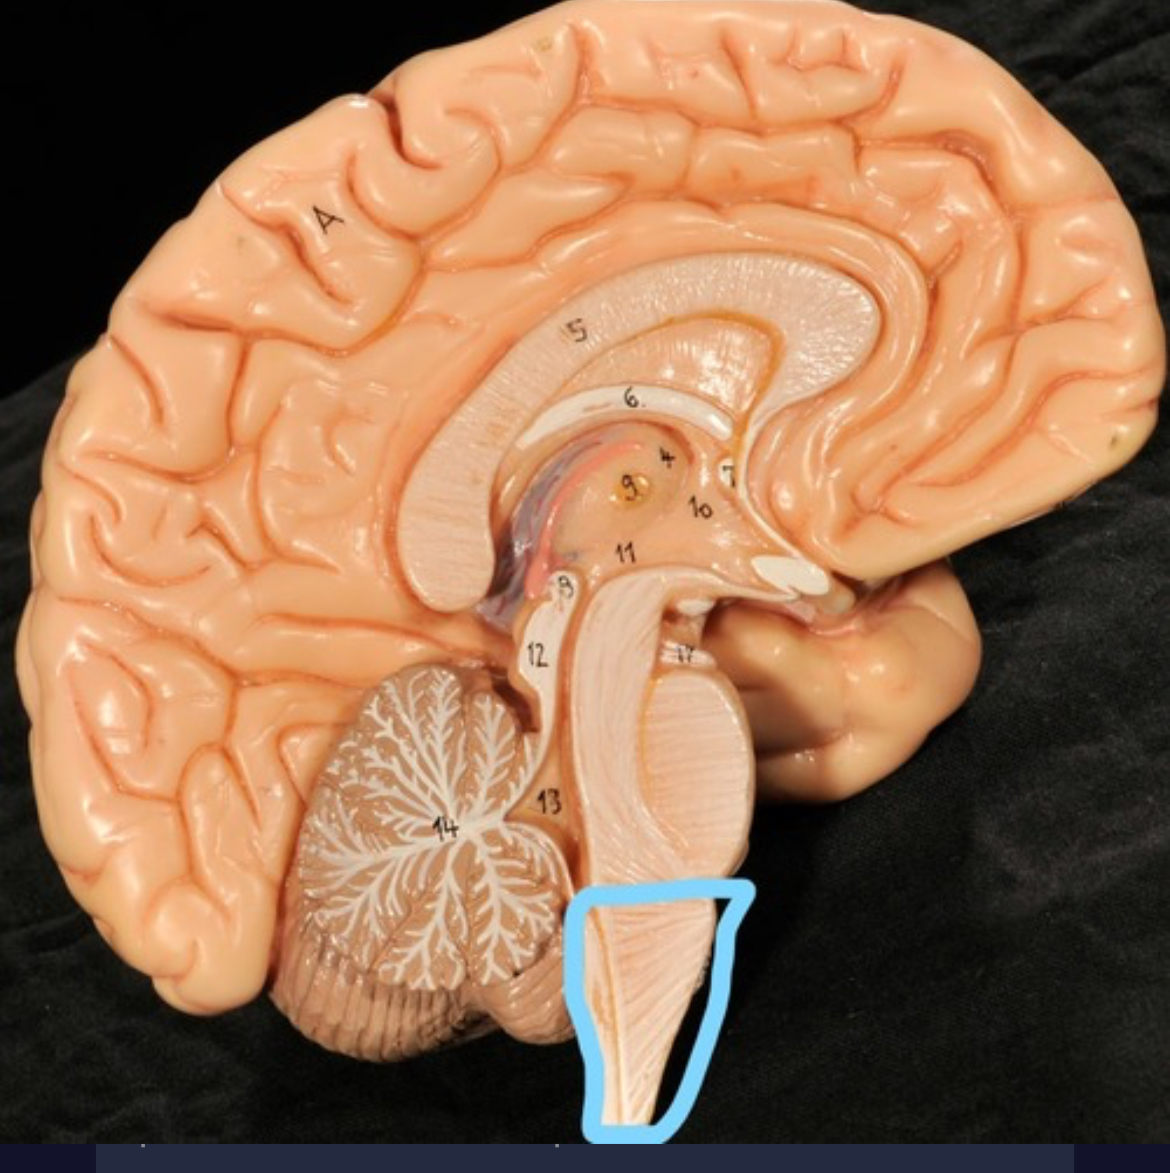

Cerebellum

Corpus callosum

Diencephalon

Thalamus

3rd ventricle

Hypothalamus

Epithalamus (pink line)

Brain stem

Pons

Medulla oblongata

Choroid plexus of 3rd ventricle

Cerebral aqueduct (midrain)

4th ventricle

central canal